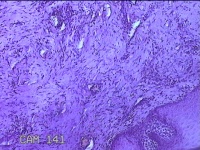

舌头肿物

性别

女

年龄

25岁

临床诊断

一般病史

无

标本名称

大体所见

灰白粉红色肿物0.7x0.5x0.2cm一个,表面光滑。

纤维性息肉